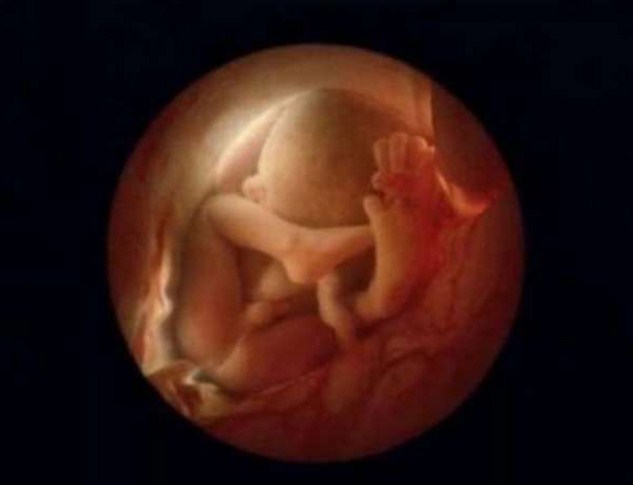

20 седмици. Зародишът е дълъг 20 сантиметра. Коса започва да се появява по главата му.

24 седмици.